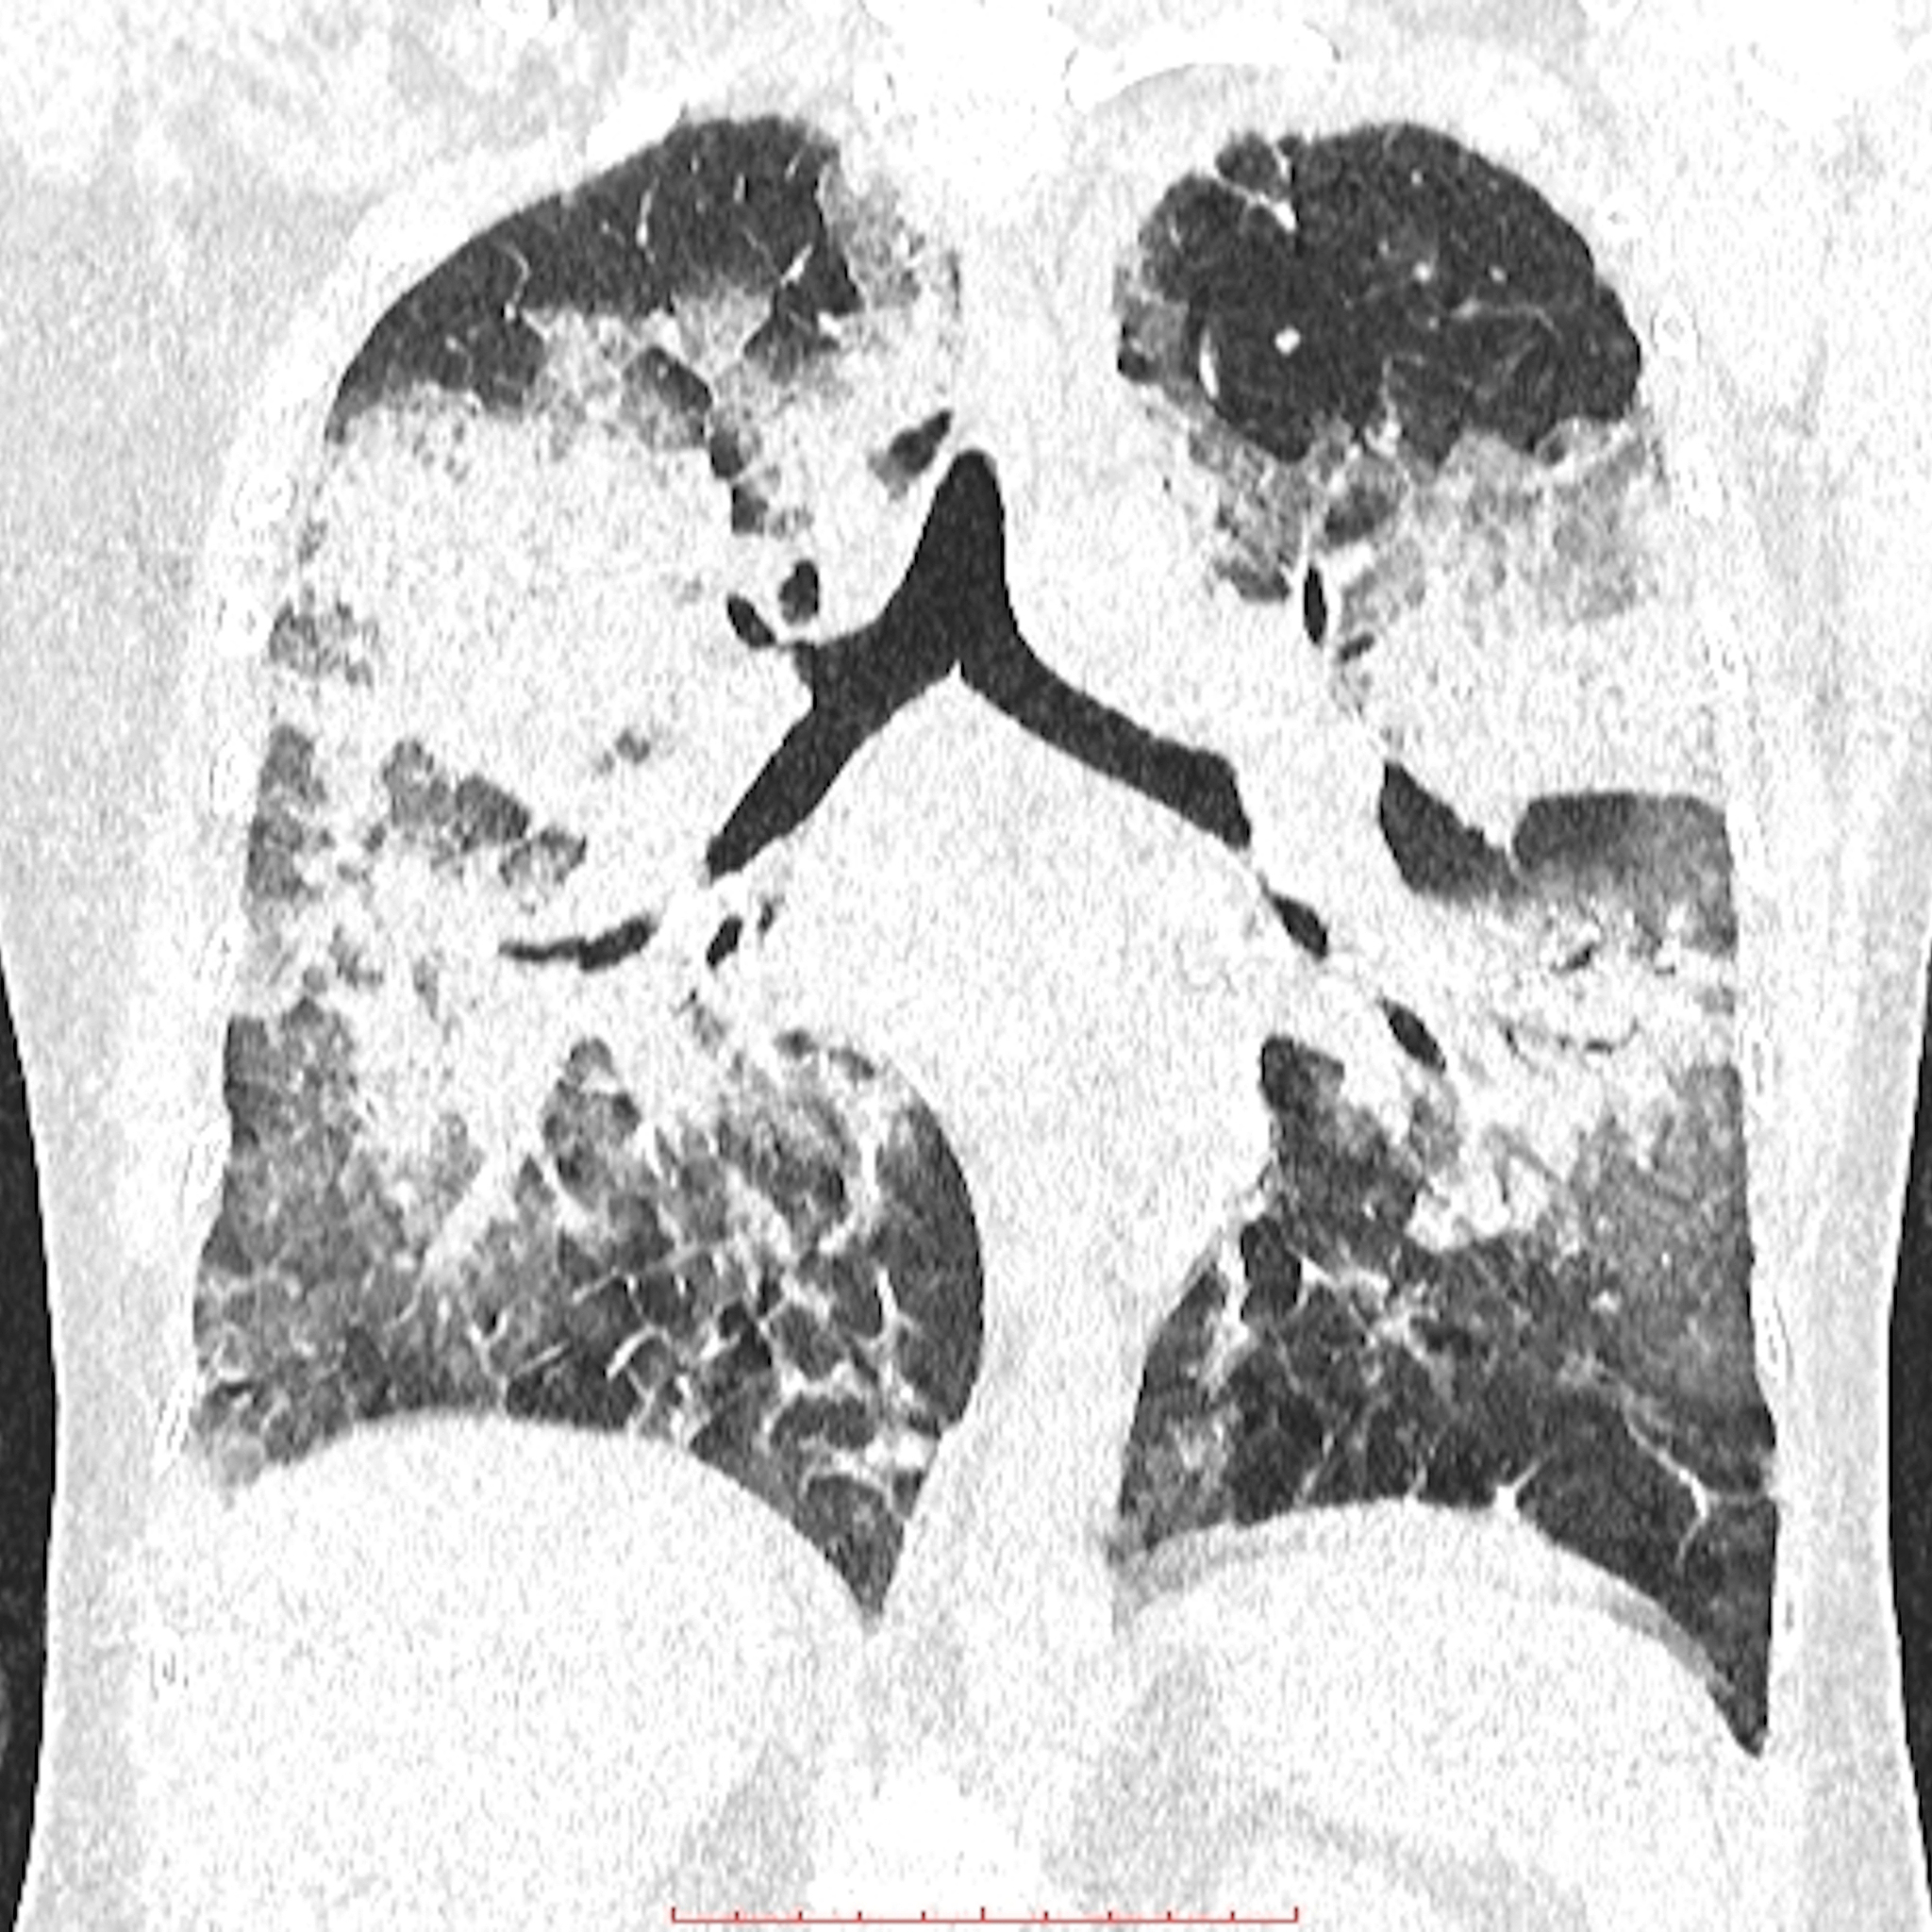

影像学检查:

胸膜间皮瘤的影像学检查是诊断该疾病的重要手段。常用的影像学检查包括胸部X线、CT、MRI等。胸部X线通常可以显示肺部和胸腔的异常阴影,但对于小肿瘤的检测能力较差。CT具有较高的诊断价值,可显示肿瘤的大小、形态、位置等信息。MRI的分辨率更高,可以更准确地显示肿瘤的位置和范围。